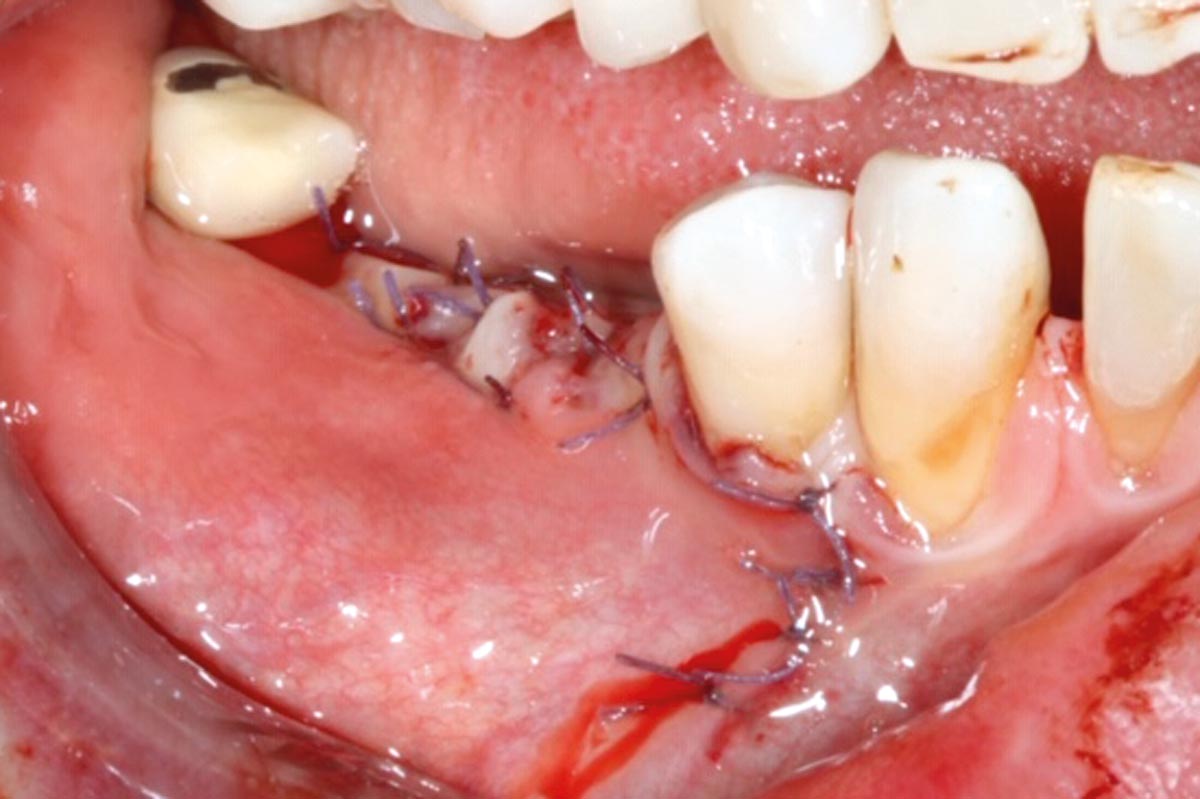

3/10 - Jason membrane® positioned and fixed.GBR with cerabone® and Jason® membrane DentalPro - Dr. A. Gargiulo

6/10 - Jason® membrane repositioned and sutured.GBR with cerabone® and Jason® membrane DentalPro - Dr. A. Gargiulo